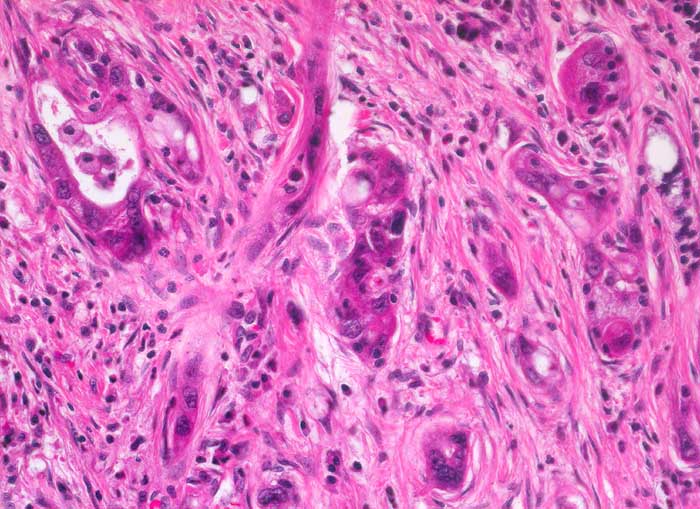

• Unregelmässige Anordnung der Drüsen (keine Läppchenarchitektur erkennbar).

• Kribriforme Drüsenformationen.

• Inkomplette Drüsen mit unvollständigen Lumina und Infiltration des Stromas durch Tumoreinzelzellen.

• Nekrotische Tumorzellen in den Drüsenlumina.

• Ausgeprägte Polymorphie und Hyperchromasie der Tumorzellkerne.

• Desmoplastisches Stroma.

Die meisten Pankreaskarzinome sind mässig bis hoch differenziert und führen zu einer deutlichen desmoplastischen Stromareaktion (derbe Konsistenz). Hochdifferenzierte Tumoren (> 1502) können sehr ähnlich aussehen wie eine chronische Pankreatitis (> 4243). Im Gegensatz zur Pankreatitis sind die neoplastischen Drüsen verformt oder rupturiert und zeigen zelluläre Atypien (grosse polymorphe Kerne mit prominenten Nucleolen). Die Tumordrüsen sind unregelmässig im Stroma angeordnet und nicht lobulär wie in der Pankreatitis. Nicht selten ist eine Nervenscheideninvasion nachweisbar (> 5884). Gelegentlich zeigen die Gänge im tumorfreien Parenchym dysplastische Veränderungen oder der Tumor breitet sich intraduktal entlang des Pankreasganges aus.